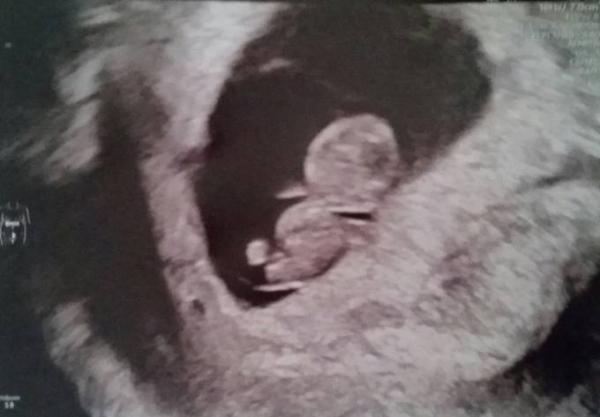

Ihr Lieben, nachdem ich vor 3 Wochen ja schonmal ein schönes Foto mit Dottersack hatte, hatte sich 1 Woche später nicht viel getan und die Ärztin datierte mich eine Woche zurück und ich schloss innerlich mit der SS ab. Alles wie bei den letzten beiden Malen. Ich war sicher, auch diesmal kein Herz zu sehen und ging bei jedem ziehen aufs Klo um zu sehen ob es blutet. Als dann die Symptome noch nachliessen, waren wir schon fast am Boden zerstört. Ich wollte nicht mal drüber schreiben. Entsprechend befangen ging ich heute zum nächsten Termin. Meiner Verzweiflung zum Trotz winkte mir ein kleiner Charlie Brown fröhlich zu und das kleine Herzchen puckerte

Bin laut Messung 8+4, Gummibärchen ist 2cm groß.